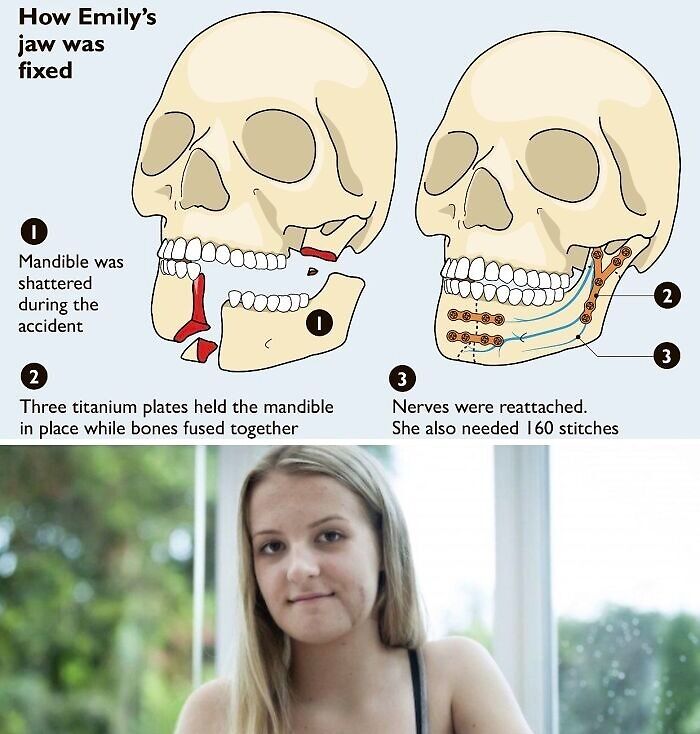

In 2019, a teenager was left with her jaw attached by just a centimetre of skin after a horror horse riding accident. Emily Eccles suffered one of the worst facial injuries her doctors had ever seen outside a war zone after an exhaust popping on a car spooked her horse.

The then 15-year-old, smashed her head into a gatepost as she fell off after the horse bolted along a country path, causing her feet to slip out of her stirrups.

She found herself holding what remained of the bottom of her face in her own hands.

Her reconstructive surgeon Ricardo Mohammed-Ali rebuilt her face during a 6-hr operation.